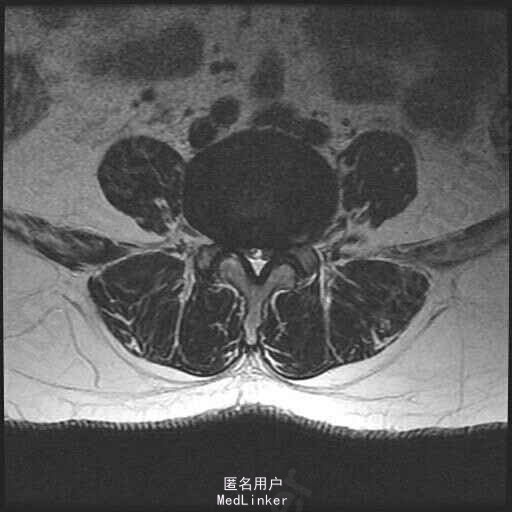

查体:脊柱无明显侧弯畸形,腰部无压痛,双上肢肌力肌张力可,无异常感觉,左下肢臀部及双下肢足背部麻木感。双侧键反射减弱,股四头肌,髂腰肌肌力四级,病理征阴性。直腿抬高试验左侧60度,右侧65度。 辅助检查:MR显示:腰椎退行性改变,L3-4.L4-5,L5-S1椎间盘突出,椎管狭窄。

诊断:L3-4.L4-5椎间盘突出,椎管狭窄 治疗: 腰椎后路减压融合内固定术